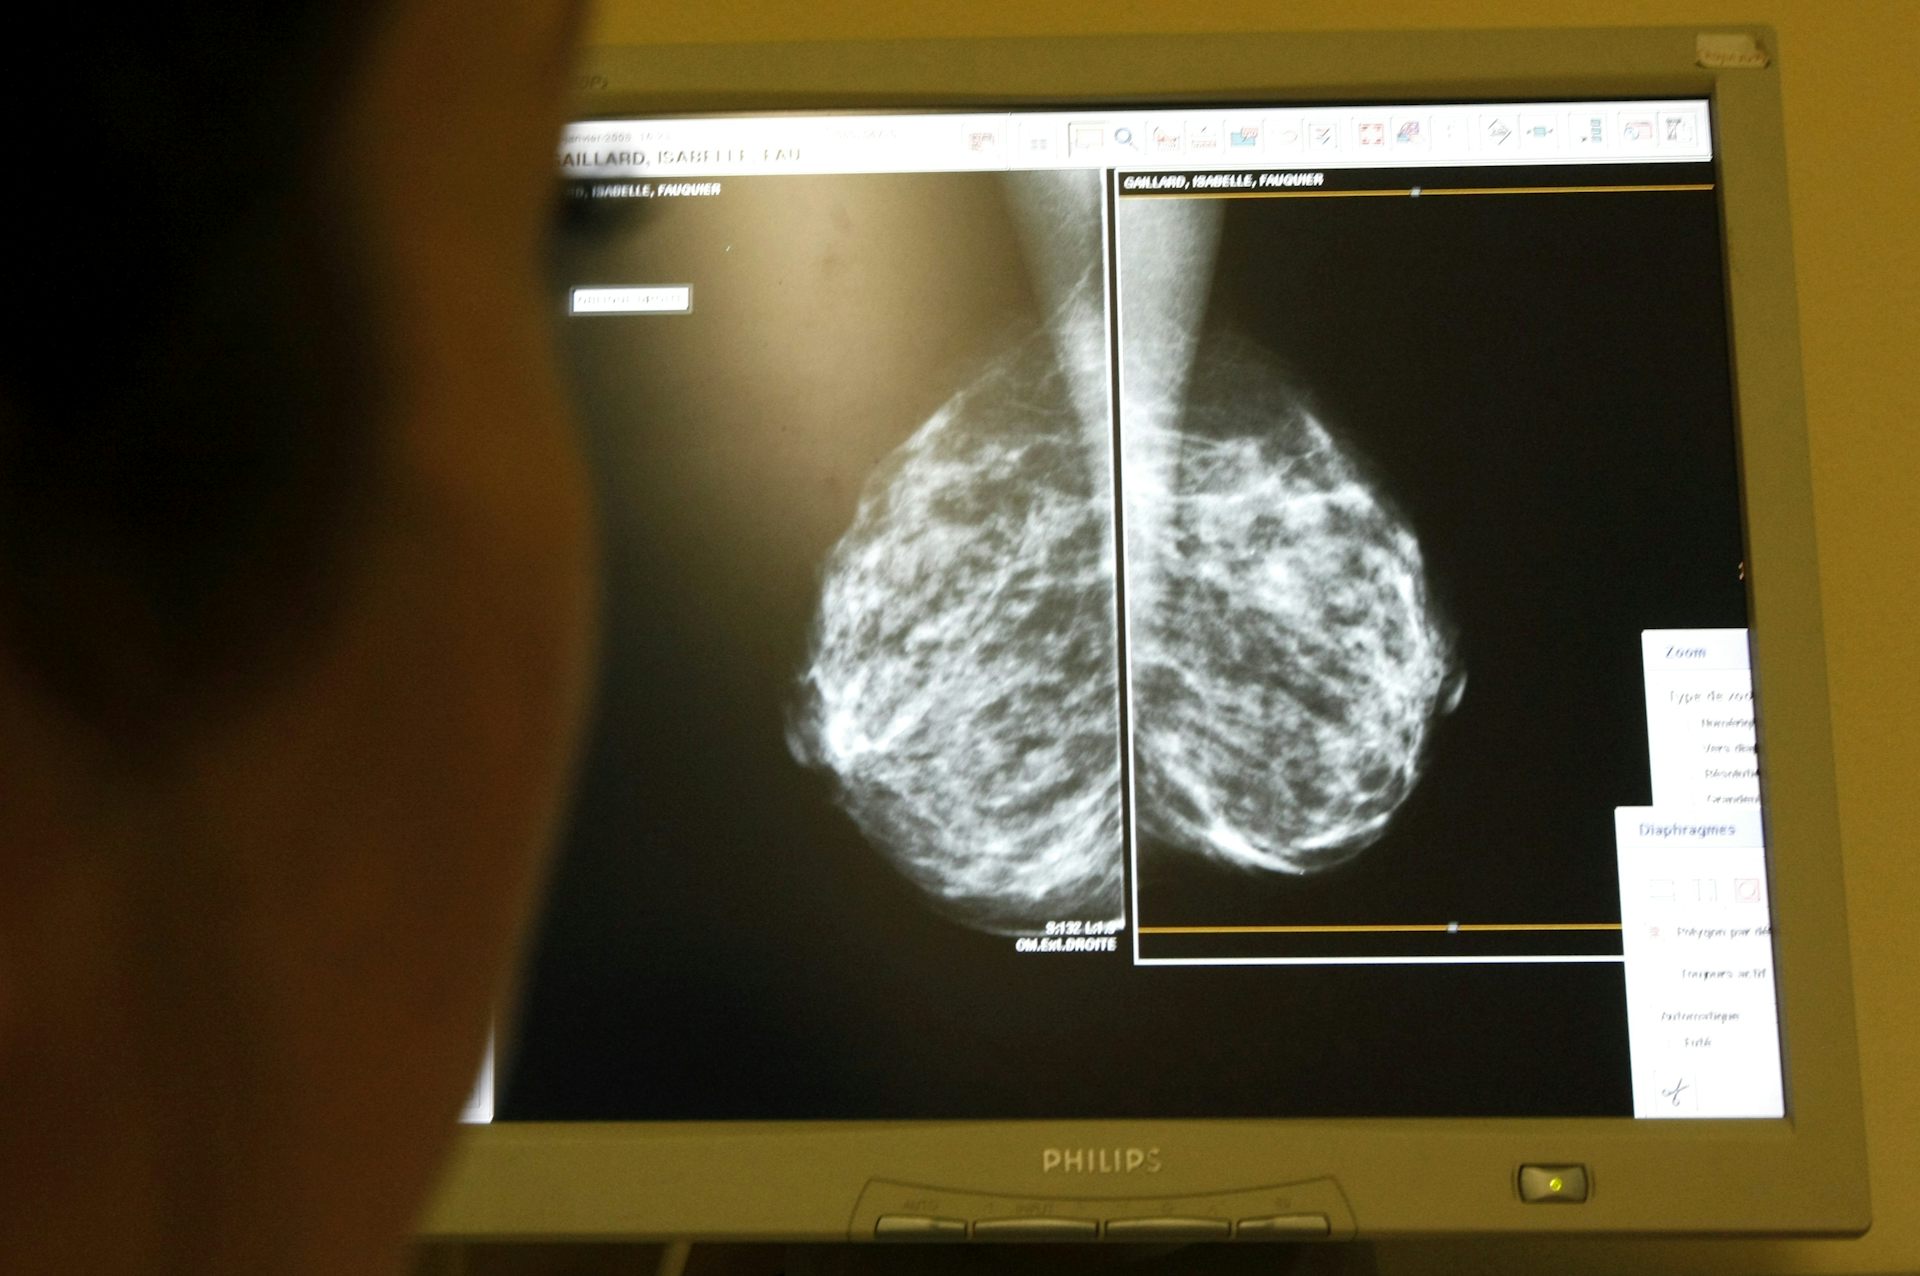

11282018 Mammography is the standard approach used to screen for breast cancer.

In all cases the decision about when to start screening mammograms should be made individually by each woman after discussing the issue with her doctor. Includes interactive tool to help you make your decision. A mammogram is the go-to imaging exam that can detect breast cancer.